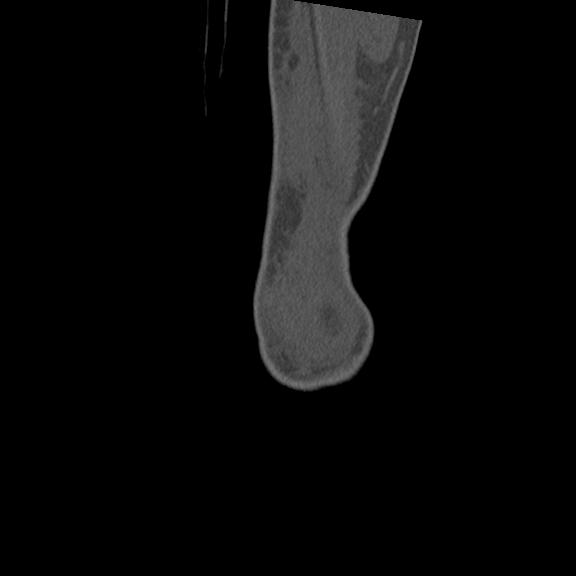

102803 1/12(キウスなし) 1/27 左下腿 4R 30歳女性 左脛骨軸内釘